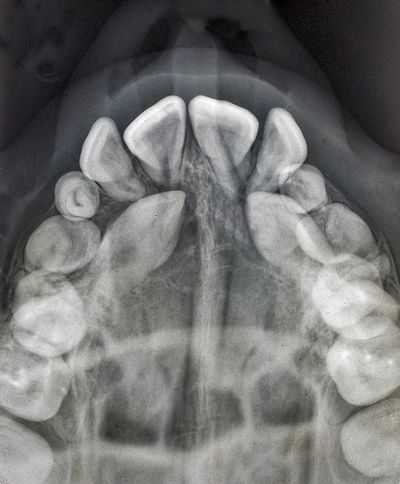

An impacted canine is a permanent canine tooth (also called a cuspid or "eye tooth") that fails to erupt into its proper position in the dental arch. Canines are the second most commonly impacted teeth after wisdom teeth, with upper canines more frequently affected than lower ones.

Canines typically erupt around ages 11-13. If a canine hasn't emerged by age 14, or if it appears to be developing in an abnormal direction, intervention is usually recommended.

Dr. Bar uses advanced diagnostic tools to evaluate impacted canines:

Early detection (ideally by age 7-10) allows for interceptive treatment that may prevent impaction altogether.